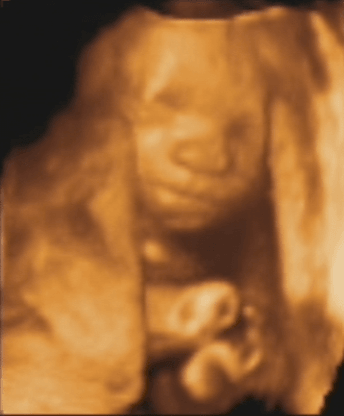

Fotki i filmiki

brzusio1.JPG